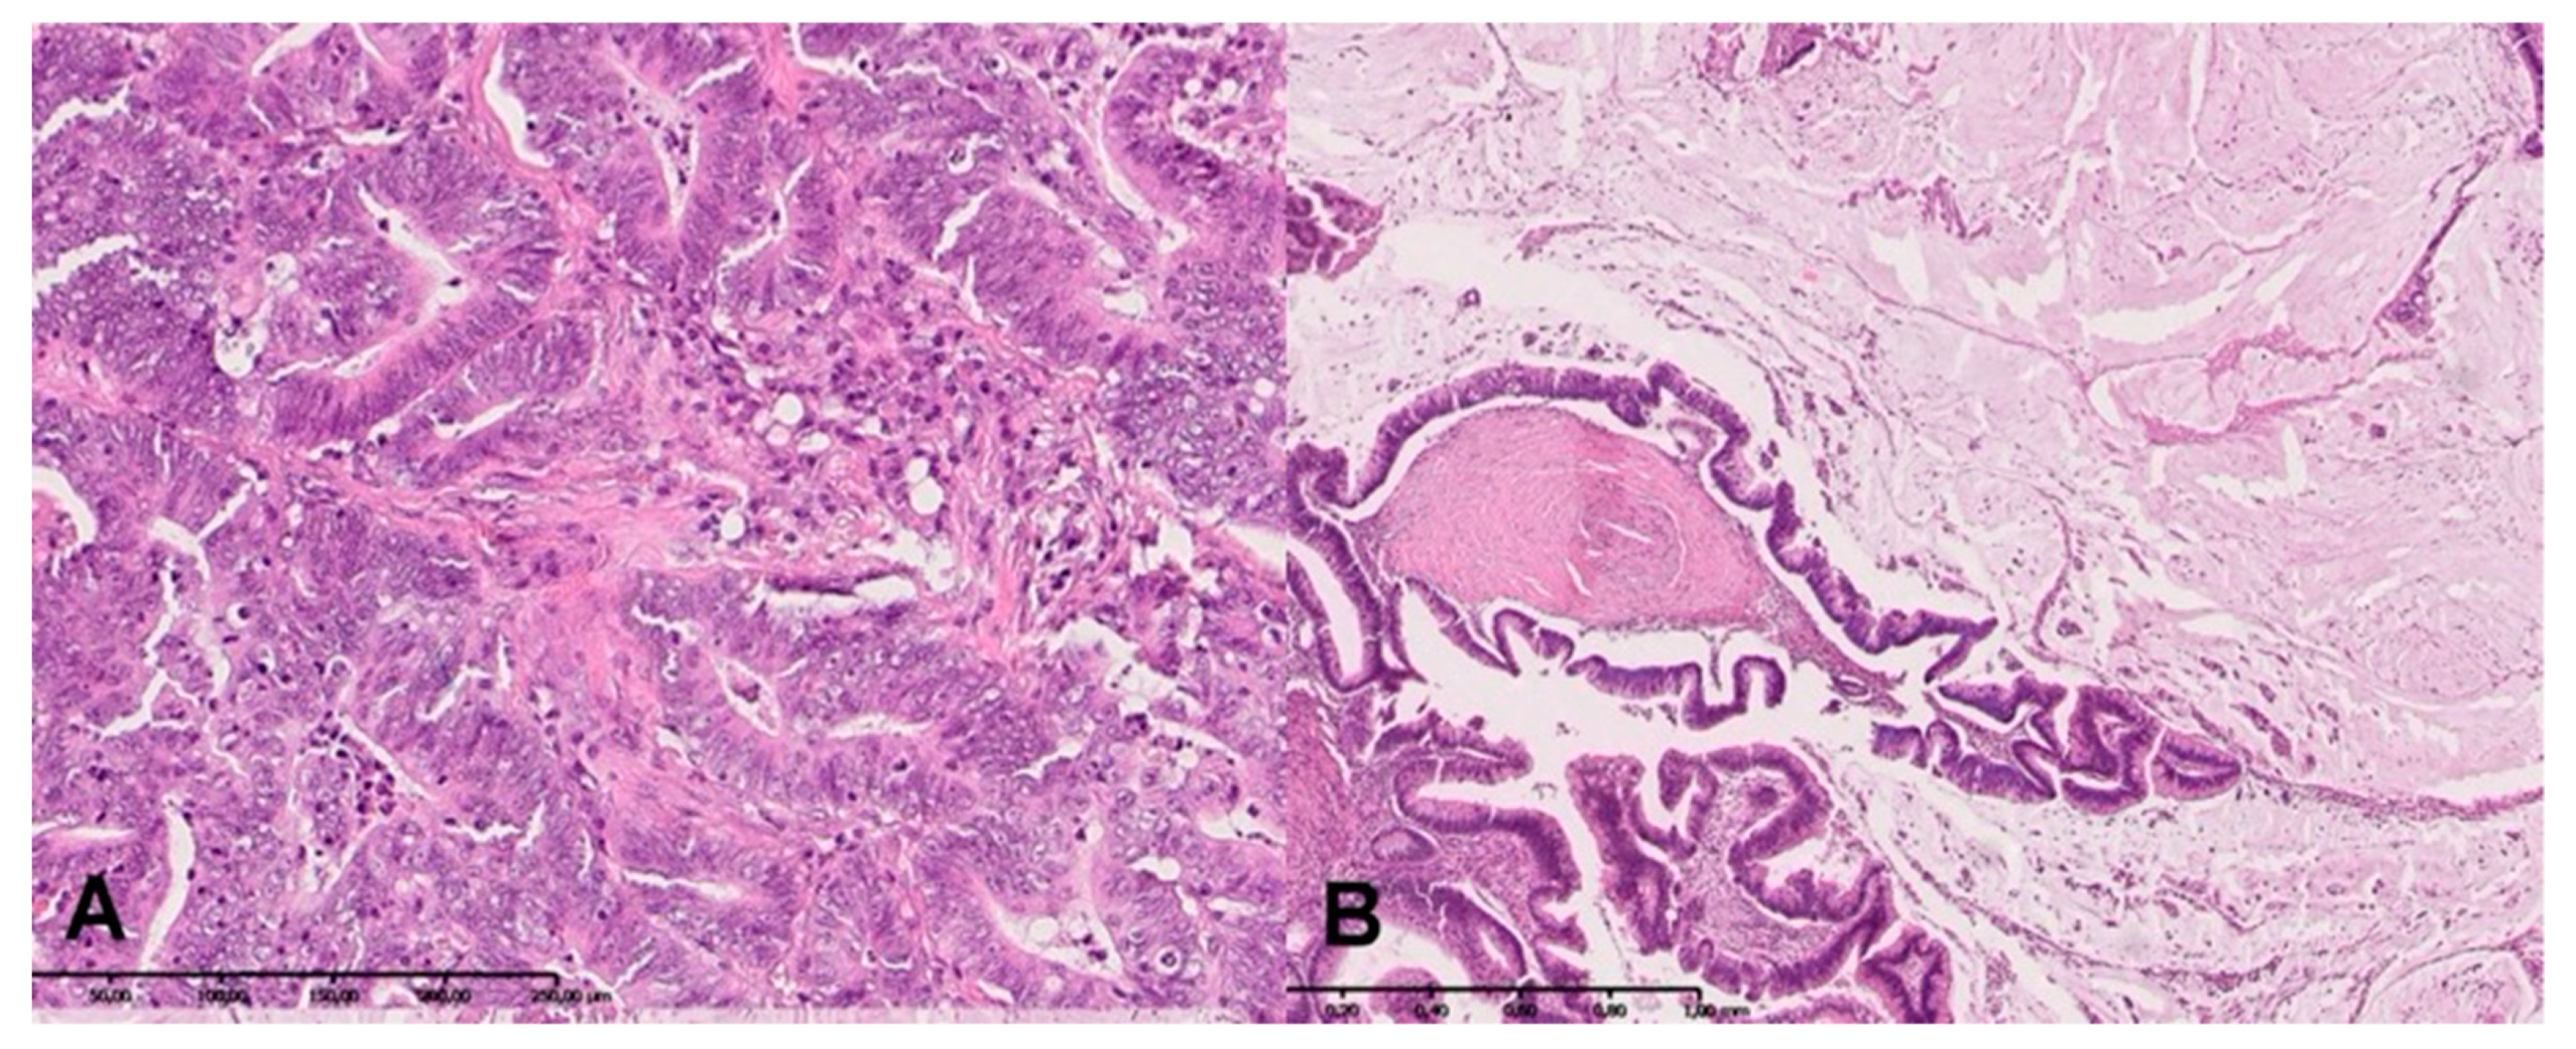

2.7. H + E Staining